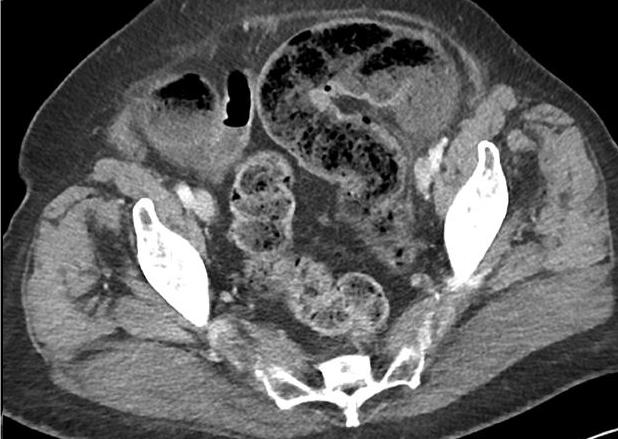

Aspect TDM une colite ischemique est :

lesion segmentaire regionale , Epaissisement de la paroi du

colon en symetrique ou lobulaire , stricture irreguliaire

segmentaire du colon ., oedeme de la muqueuse en forme signe

de cible " target sign ", presente de gas intramurale ou a

la veine porte , thrombus de artere ou veine mesenterique

superieur .

Aspect TDM une colite

ischemique avec image de gas intramurale du colon

sigmoide . Image radiologique TDM en coupe axiale a

travers sacrum S2 |